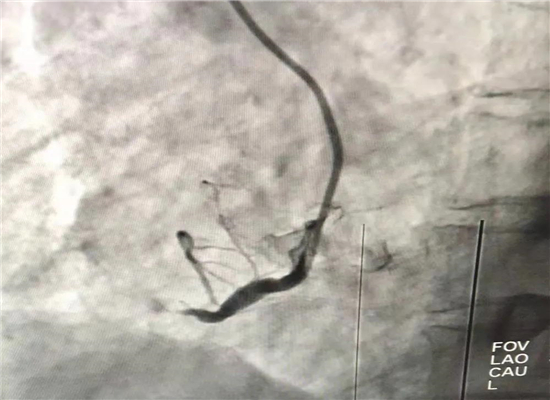

19时13分左右,一名患者因晚饭后行走不稳而请求出诊,急诊医学科医护人员火速赶往现场,到诊时测生命体征,输液后接回急诊医学科,回科后做心电图检查,诊断为急性心肌梗塞,随即通知心血管内科会诊,确定做急诊介入治疗,20时30分进入导管室,杨勇主任、张轩副主任共用21分钟就实现了心肌再灌注,挽救了患者生命。

介入手术后